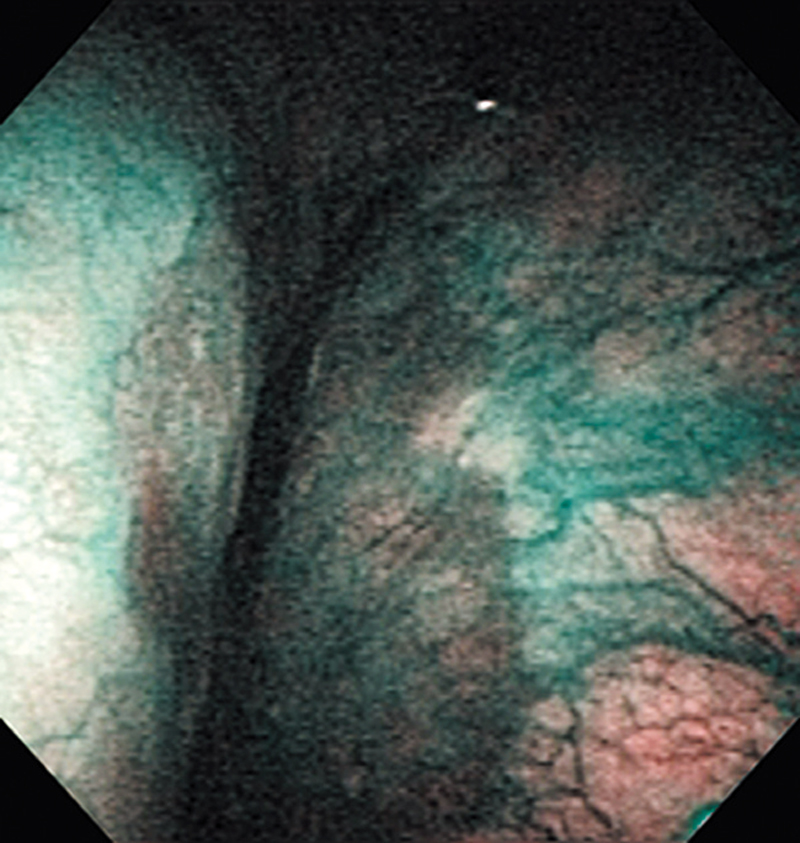

Hypopharynx Cancer (Right Pyriform Sinus) Aged 45, male

NBI

The lesion was detected on the right pyriform sinus in a head/neck cancer screening with NBI laryngopharyngoscopy before an esophageal carcinoma surgery.

The NBI image showed it as a well demarcated relatively depressed brownish lesion. In the conventional white light image, a slight reddening was observed in the same area.

The lesion was treated with endoscopic mucosal resection and diagnosed as a carcinoma in situ.